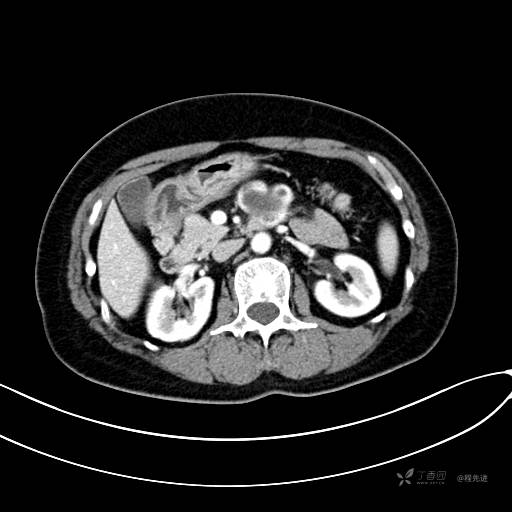

CT增强动脉期